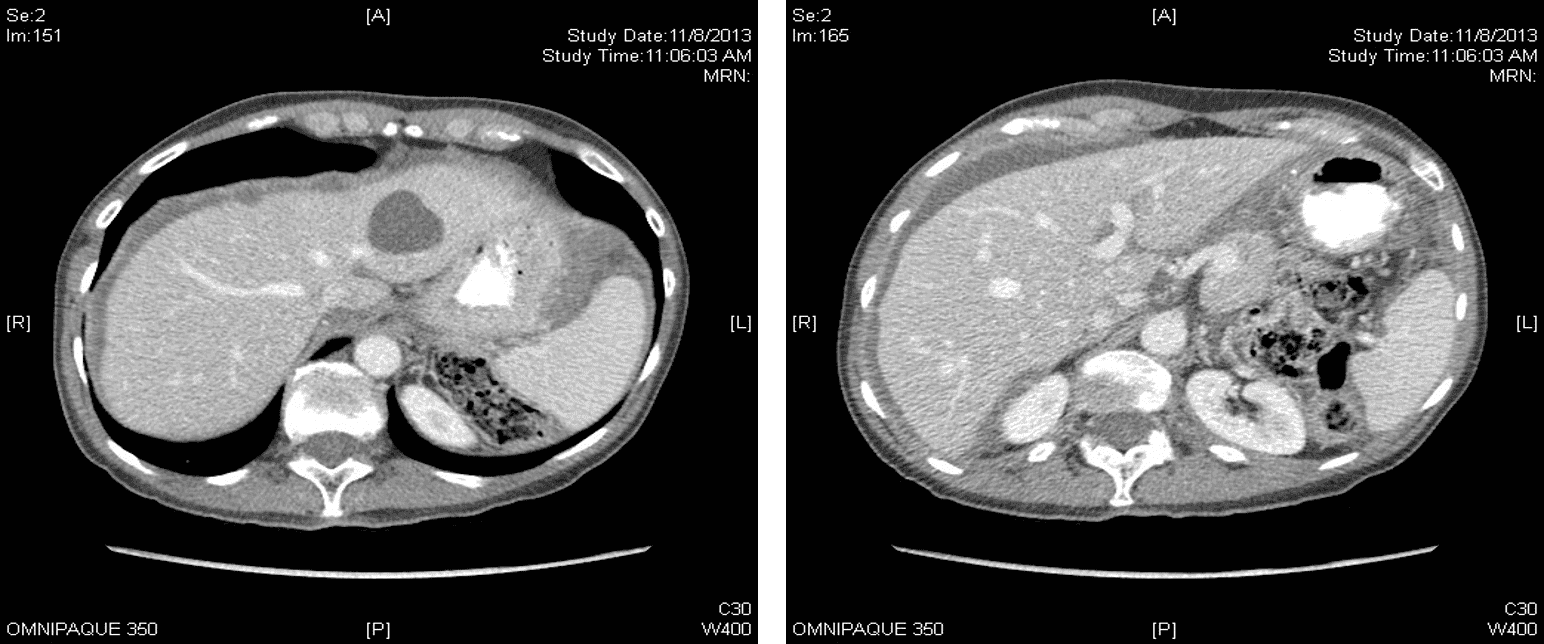

Imaging workup for appendiceal adenocarcinoma may include CT or MRI and selective use of PET/SPECT (single photon emission CT). Tumors of at least 15 mm may demonstrate soft-tissue enhancement or cystic dilation [1]. Partial or complete bowel, urinary, or biliary obstruction may be seen in symptomatic patients and typically signifies high-grade serosal and or mesenteric disease. Diffuse mucinous ascites may be observed with liver scalloping (Fig. 2), a hallmark of mass effect from the mucin, and women may have very large adnexal cystic masses [1]. In addition to identifying specific features, the peritoneal carcinomatosis index (PCI) is an important tool in determining both treatment strategy and prognosis [1].